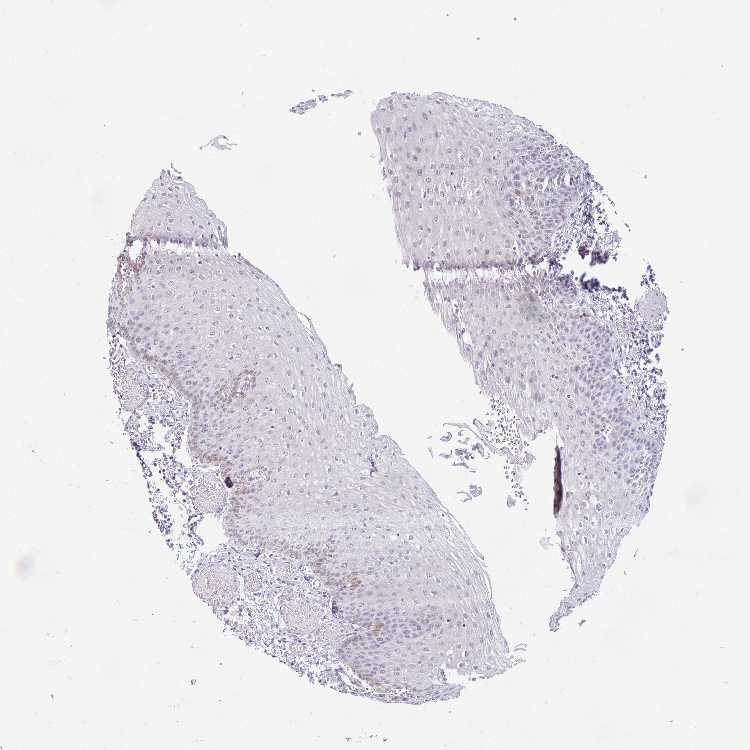

ESOPHAGUS - Antibody stainingi

Antibody staining in the annotated cell types in the current human tissue is reported as not detected, low, medium, or high, based on conventional immunohistochemistry profiling in selected tissues. This score is based on the combination of the staining intensity and fraction of stained cells.

Each image is clickable and will lead to virtual microscopy that enables deeper exploration of all samples and also displays staining intensity scores, fraction scores and subcellular localization as well as patient and tissue information for each sample.

Antibody HPA053250Antibody HPA055824

Squamous epithelial cells Not detectedLow